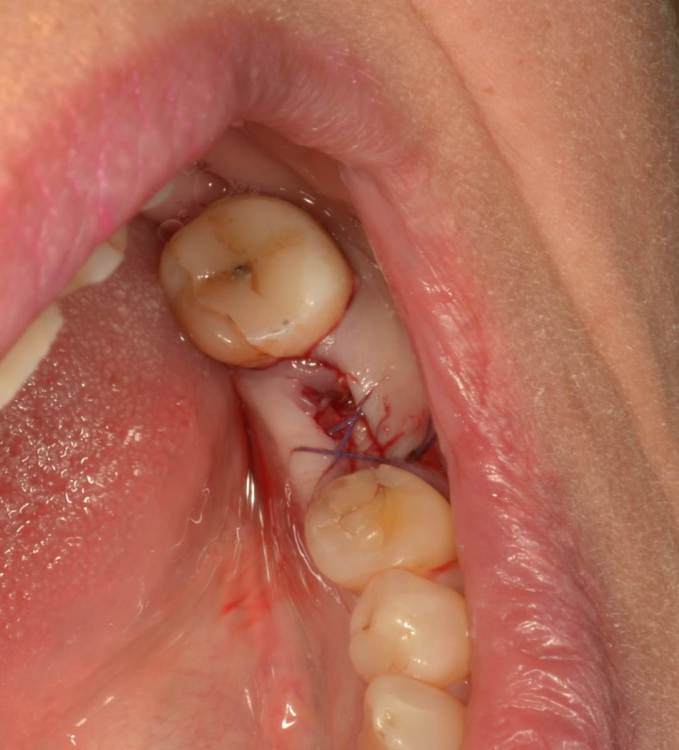

Большой Зеленый Опубликовано 27 мая, 2022 Поделиться Опубликовано 27 мая, 2022 Через 9 лет. Есть немного рецессии.. 2 Ссылка на комментарий

pit Опубликовано 27 мая, 2022 Поделиться Опубликовано 27 мая, 2022 4 часа назад, Большой Зеленый сказал: Через 9 лет. Есть немного рецессии.. Это связано исключительно с вестибулярной позицией импланта. Это как раз к вопросу про те минимальные 2мм до вестиболярной стенки, вне зависимости есть она или ты ее создаешь. Ссылка на комментарий

Большой Зеленый Опубликовано 27 мая, 2022 Поделиться Опубликовано 27 мая, 2022 4 часа назад, pit сказал: Это связано исключительно с вестибулярной позицией импланта. Это как раз к вопросу про те минимальные 2мм до вестиболярной стенки, вне зависимости есть она или ты ее создаешь. С тех пор я стал хитрее умнее и опытнее ))) 1 час назад, alboard сказал: А в чем смысл ее сохранности, если препарируя под имплантат вы все равно ее в большинстве случаев сносите? Первичная стабильность импланта зачастую достигается только перегородкой.. Ссылка на комментарий

Женька Опубликовано 27 мая, 2022 Поделиться Опубликовано 27 мая, 2022 @Большой Зеленый это вроде ваш старый кейс? напомните пожалуйста, тут присыпка+мембранинг вестибулярно и вестибулярным лоскутом слегка послабленным всё закрыли? Ссылка на комментарий

Большой Зеленый Опубликовано 28 мая, 2022 Поделиться Опубликовано 28 мая, 2022 12 часов назад, Женька сказал: @Большой Зеленый это вроде ваш старый кейс? напомните пожалуйста, тут присыпка+мембранинг вестибулярно и вестибулярным лоскутом слегка послабленным всё закрыли? Да все так и есть как Вы и описали. Работе почти 10 лет. Присыпка мп3 от остеобила сверху "ильгамовская" губка . Считаю что результат вполне удовлетворительный. Рецессия обусловлена как уже сказали выше вестибулярным положением импланта ,ну и недозаглублен чуток. Ссылка на комментарий